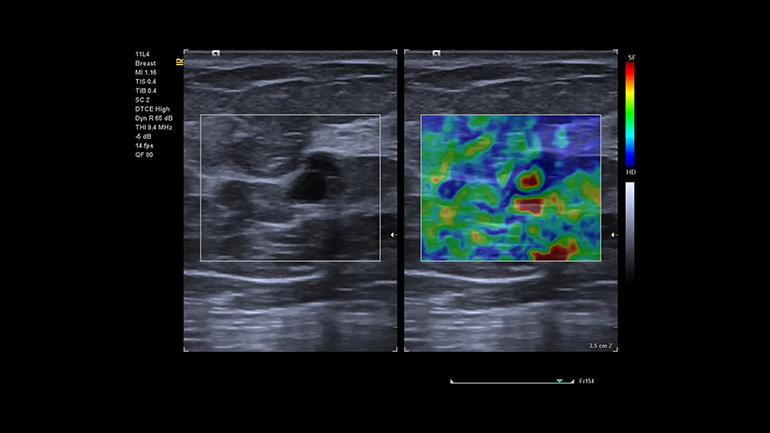

Предоставление высококачественной медицинской помощи подразумевает возможность сканирования практически любых пациентов независимо от их телосложения, веса или состояния. Благодаря своей клинической универсальности в сочетании с ведущей технологией эластографии УЗ-система ACUSON Juniper позволяет расширить спектр ультразвуковых исследования практически для всех категорий пациентов и диагностических ситуаций.

Технология оценки скорости распространения поперечной волны и эластичности в выбранной области интереса (Virtual Touch quantification). Метод измерения скорости поперечных (сдвиговых волн) в режиме реального времени, в котором используются низкочастотные акустические импульсы (ARFI), генерируемые непосредственно ультразвуковым датчиком. Оценка скоростей сдвиговых волн в выбранной врачом зоне интереса коррелирует с показателями жесткости ткани. Технология качественной визуализации относительной эластичности ткани eSie Touch. Метод качественной и количественной эластографии в режиме реального времени, который позволяет вычислять и отображать на экране относительную жесткость исследуемой ткани. Метод eSie Touch дает возможность сгенерировать эластограмму за счет применения к ткани последовательных циклов мануальной компрессии во время стандартной визуализации в B-режиме.

Технология качественной визуализации относительной эластичности ткани eSie Touch. Метод качественной и количественной эластографии в режиме реального времени, который позволяет вычислять и отображать на экране относительную жесткость исследуемой ткани. Метод eSie Touch дает возможность сгенерировать эластограмму за счет применения к ткани последовательных циклов мануальной компрессии во время стандартной визуализации в B-режиме. Векторный анализ кардиомиокинетики (syngo Velocity Vector Imaging). syngo Velocity Vector Imaging поддерживает оценку глобальной и региональной механики движения сердечной мышцы, включая глобальную продольную деформацию.